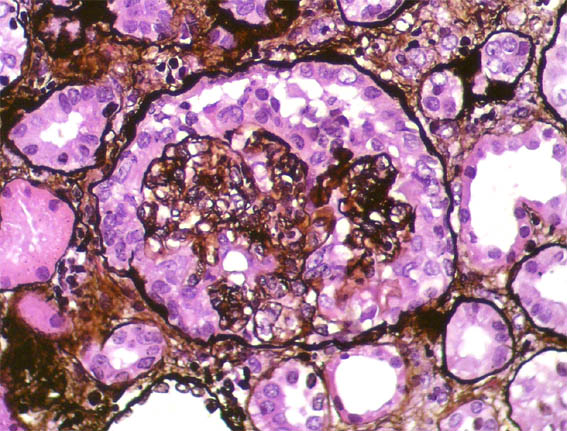

Figure 6. Methenamine-silver, X400.